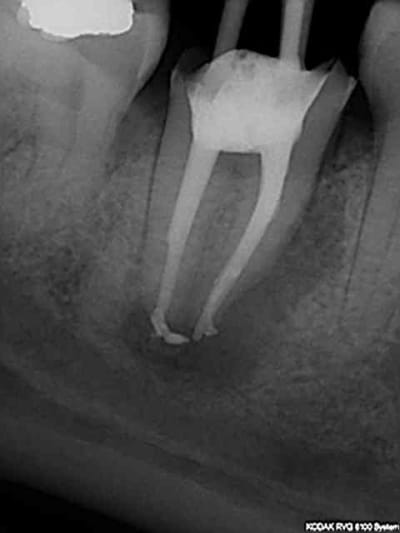

> @Chicot29: Tes endos sont superbes. Ce type de travail n'a aucune valeur pour

> santeclair et les autres guignols. Il n'y a que le prix, le prix, le prix. Tout

> le discours sur la qualité et le respect des normes de bonne pratique est de

> l'enfumage. Le but c'est de baisser le prix UN POINT C'EST TOUT. Il y a un

Ca c'était le cas de 14 h, voici le cas de 11h plus délicat. On verra ce que ca donne dans le temps ( finition au R40). C'est un peu creux en ce moment, heureusement qu'il y a des traitements réalisés conformément aux données acquises de la science à reprendre !)))))